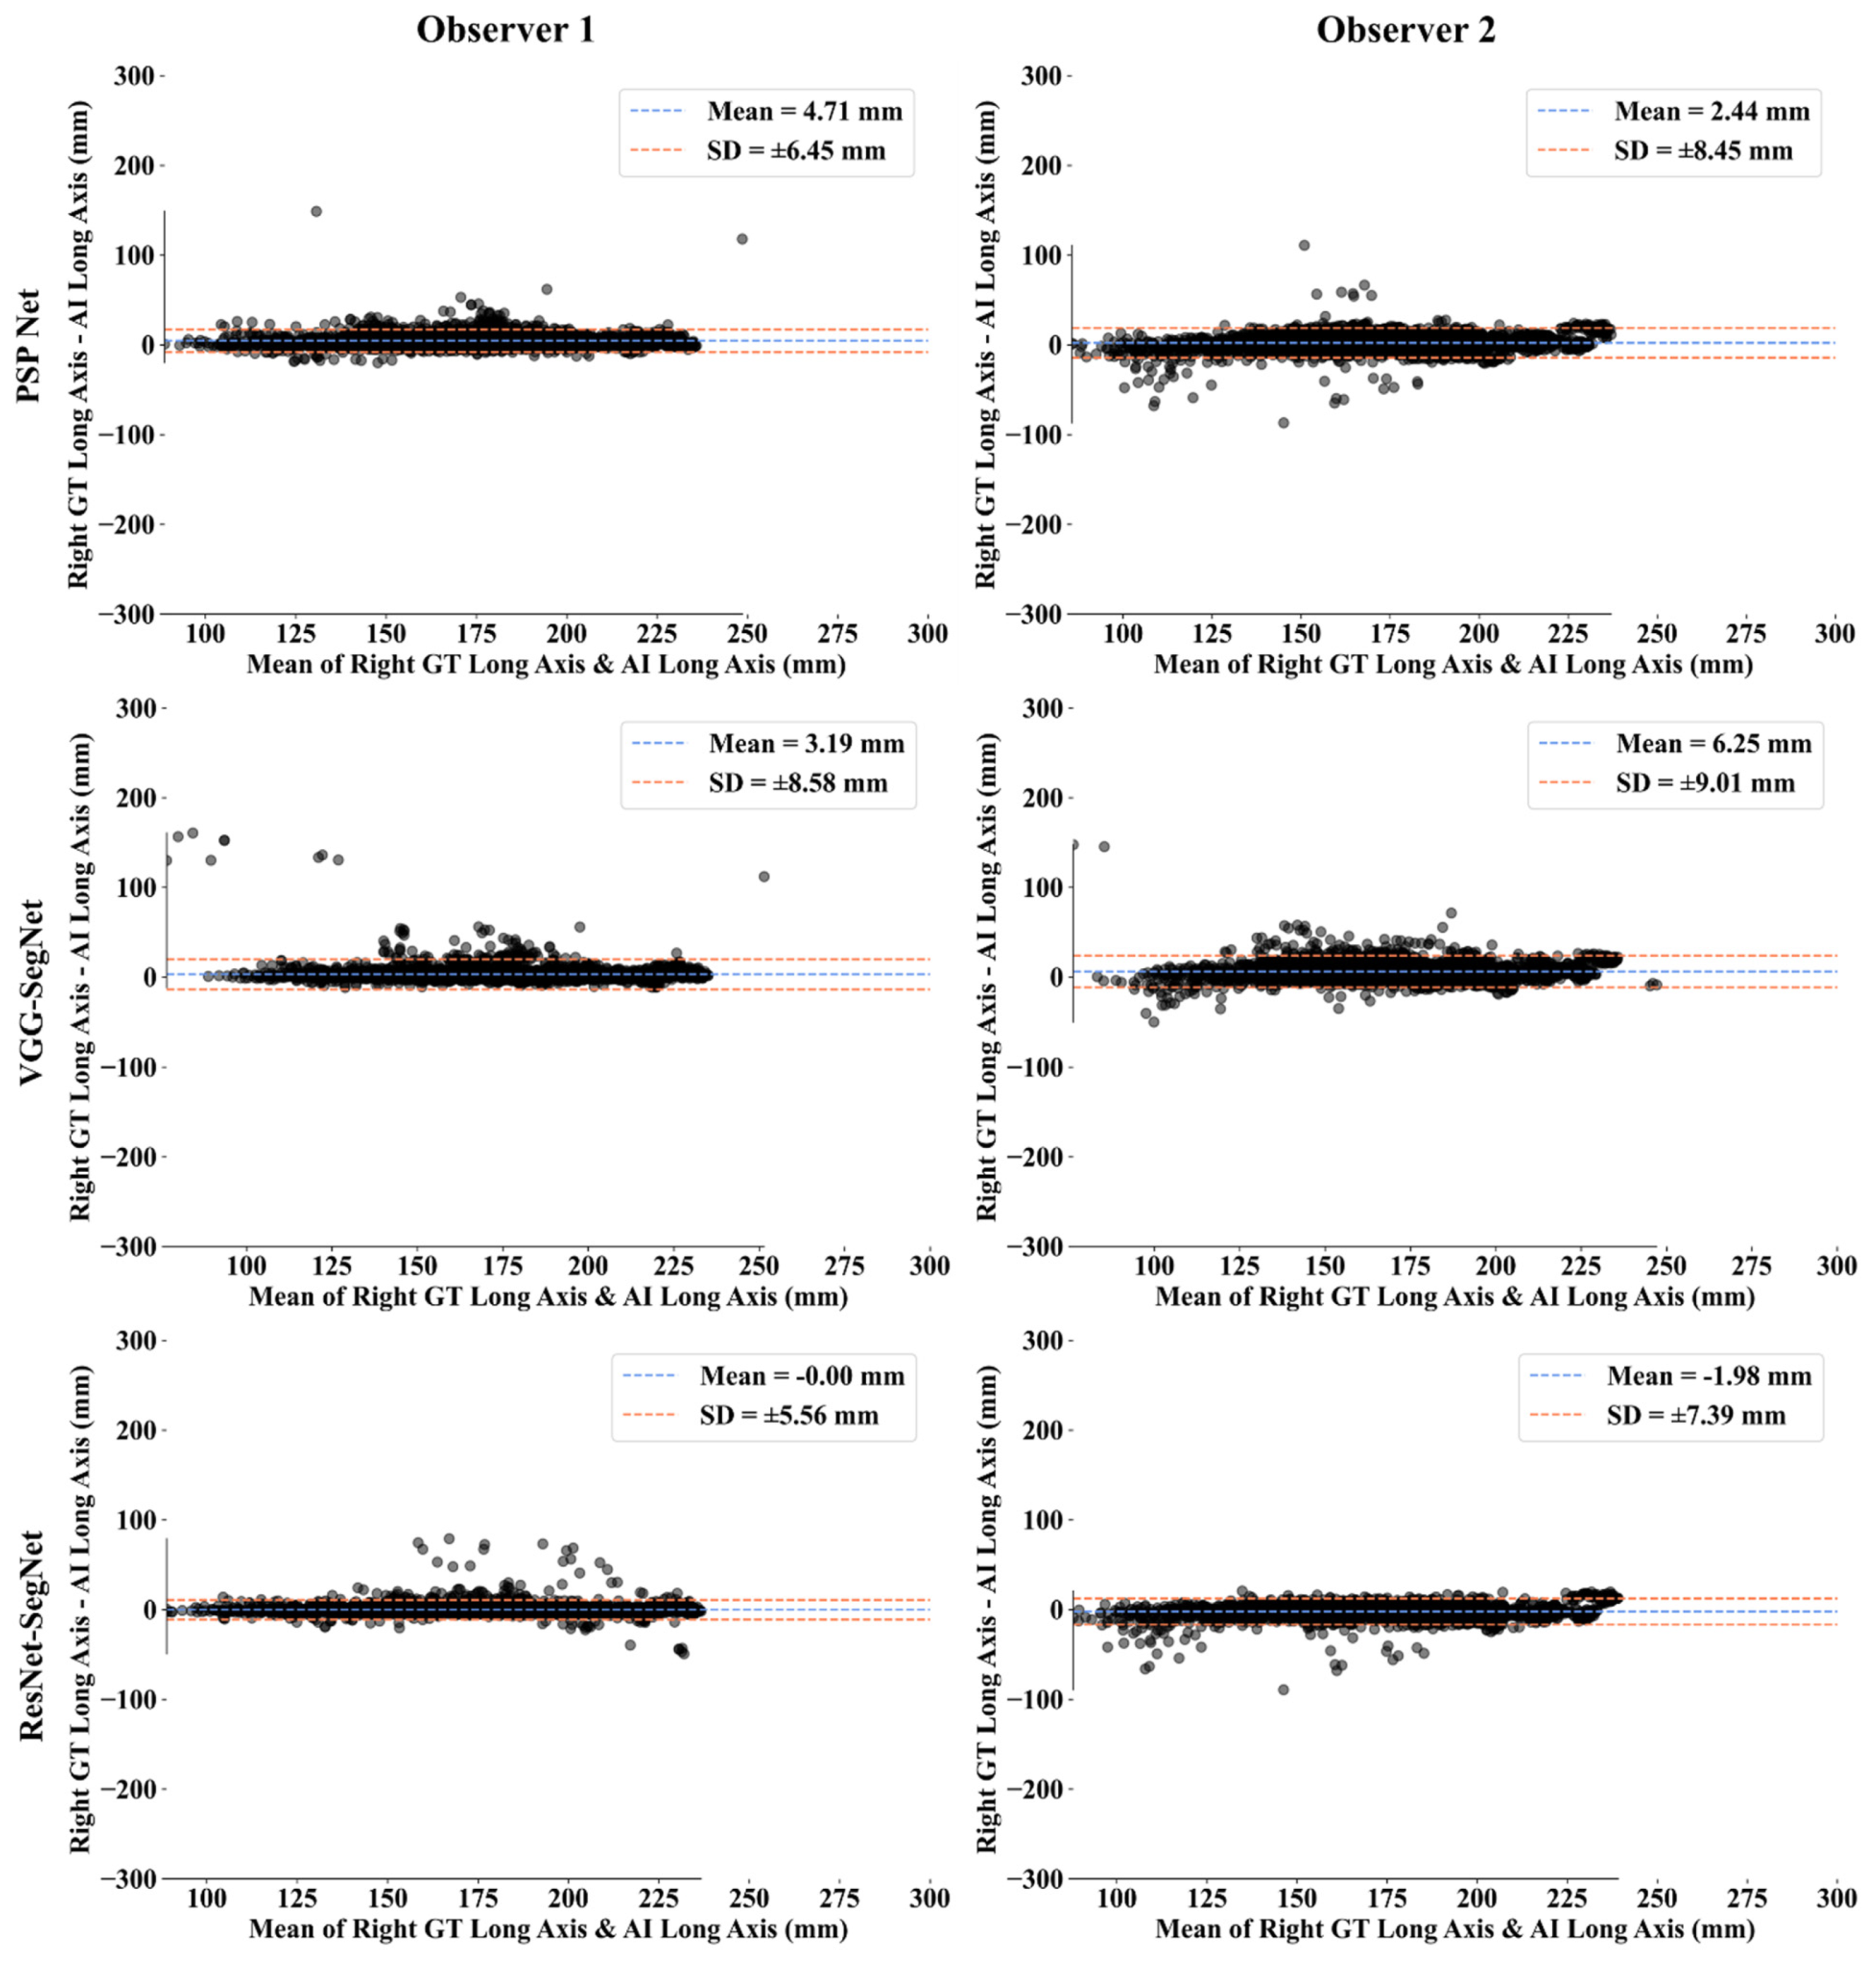

Bland-Altman Plots for Lung Long Axis Error

Statistical Tests